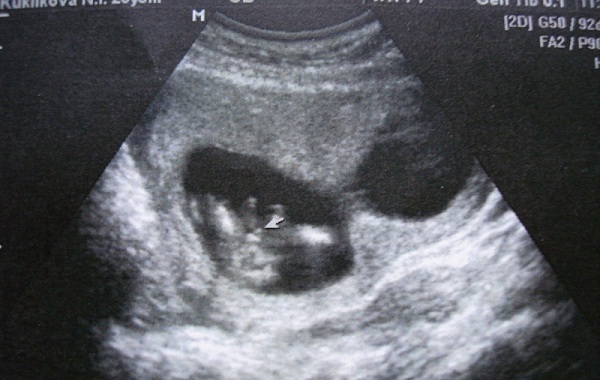

Хотите фото 13 недель и 4 дня?

По-моему, там все прекрасно видно и понятно. Это мальчик. И пока сомневаться не приходилось.

И я еще пока в своем уме, я ЗНАЮ как шевелится ребенок. Ребенок начинает непроизвольно дергаться с 12 недели, с 16 он начинает слышать и ОСОЗНАННО делать движения и к 18-20 неделям они становятся настолько сильными, что мама может начать их ощущать. Вот только чувствительность у всех разная. Я чувствую свою овуляцию и знаю в каком именно яичнике. Я ходила обследоваться, ибо не понимала что это за боли такие, оказывается овуляция. Мне врач объяснила, что после родов чувствительность стала намного выше у меня. Да 15-16 неделя как то вне сомнений, что это как минимум 4-й месяц.

а может это пуповина....

Яйки с писькой?

Нет, Ань, это не пуповина. Мы в разных ракурсах смотрели. У меня ребенок в соседней комнате находится, пока сомнений в том, что это оказался мальчик - нету.